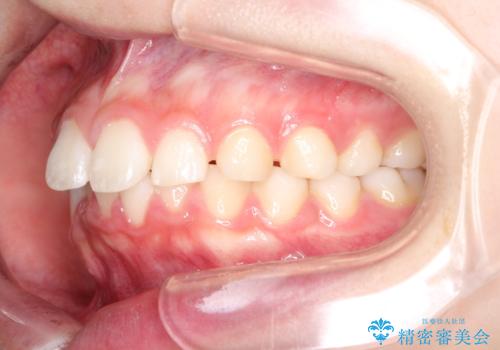

【インビザライン】出っ歯を引っ込めたい。

- 前歯の隙間と、出っ歯に見えることを主訴に来院されました。

できるだけ目立たない装置をご希望されましたので、インビザラインにて治療を行いました。

治療中は、できるだけ前歯を下げることができるように”顎間ゴム”を使用します。

”顎間ゴム”を利用することで、奥歯を後ろに動かす力を強めることができます。